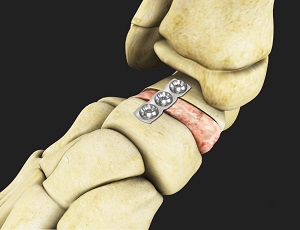

Revision Joint Replacement

Revision total ankle replacement is a surgical procedure to replace a failed or malfunctioning...